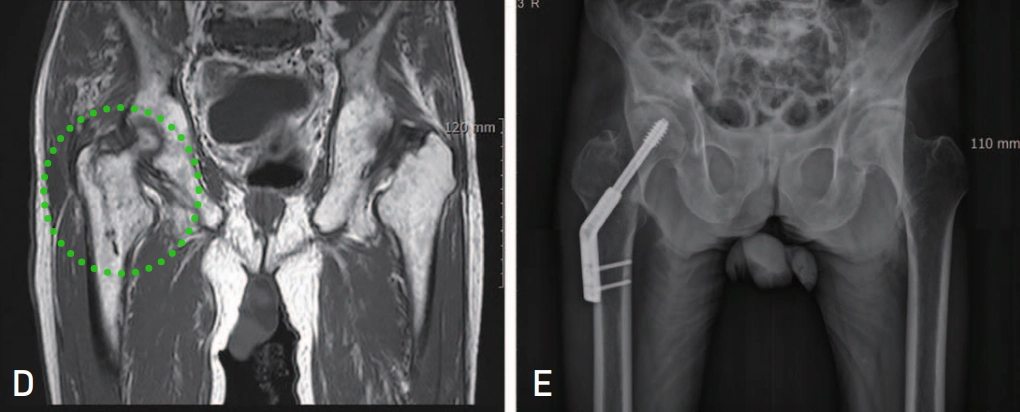

▲ 图示87岁女性患者,摔伤致右髋部疼痛。A:X线检查提示右髋孤立性大转子骨折;B:骨扫描提示孤立性大转子骨折;C:MR提示右股骨粗隆间骨折。

7例同时行CT和磁共振检查的患者中,3例CT提示为孤立性大转子骨折,但磁共振显示所有7例患者的骨折均延伸至转子间内侧1/2皮质,其中4例接受了手术治疗。